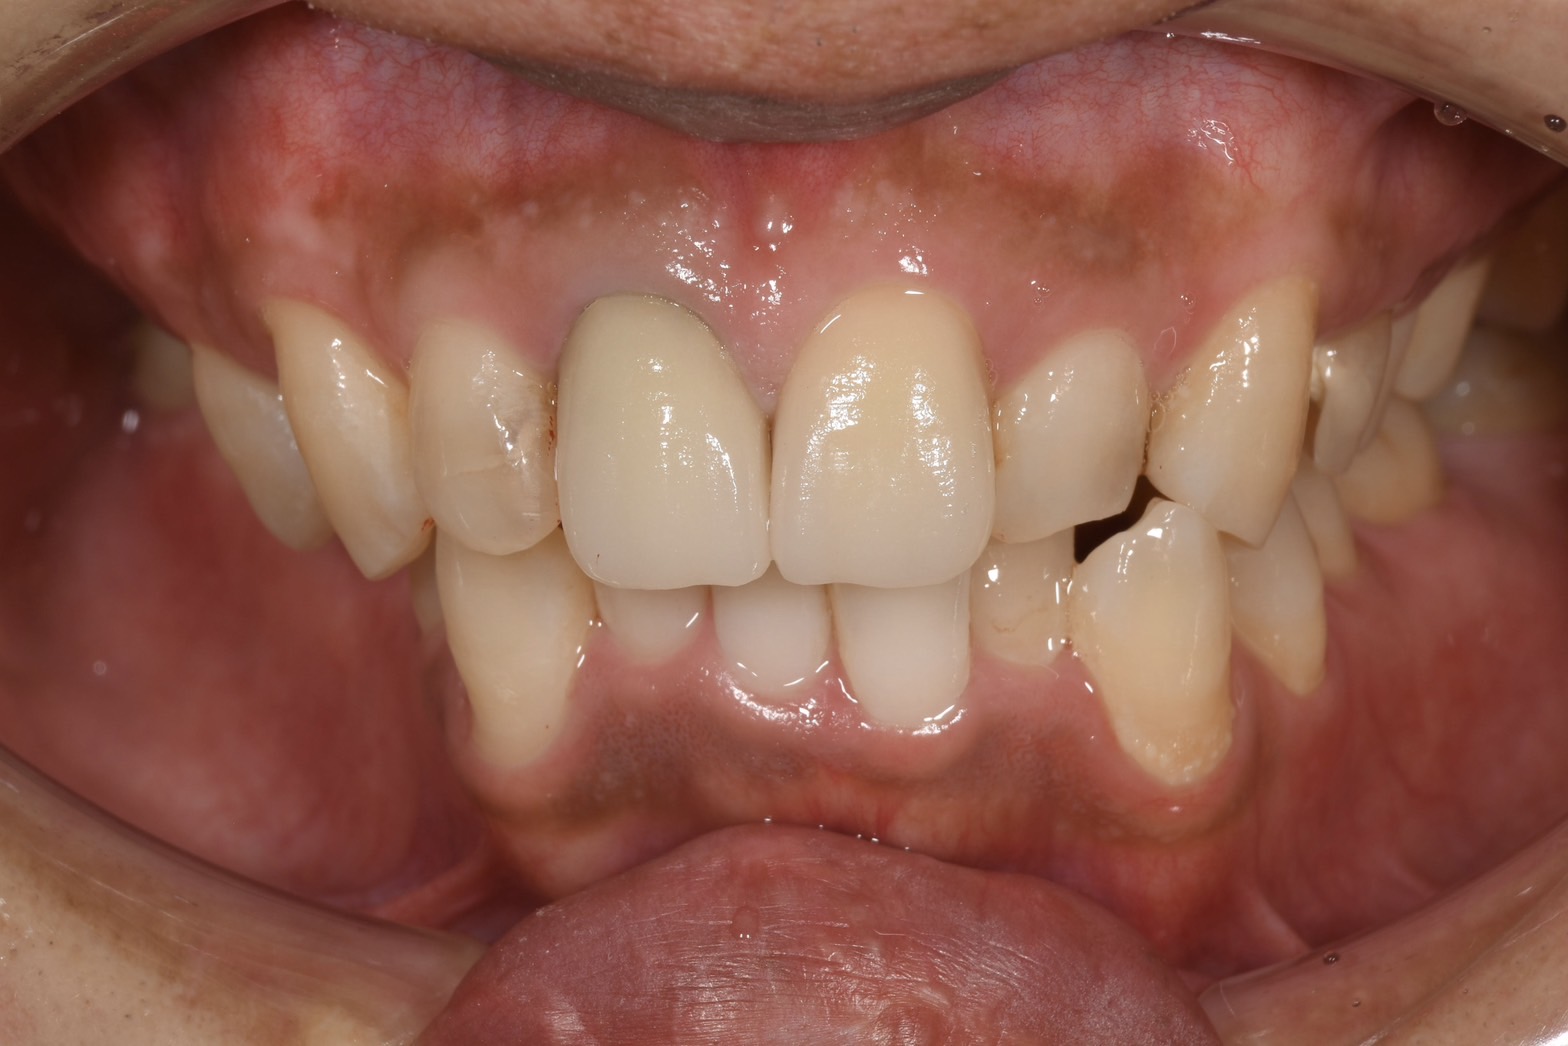

保険の前歯被せ物には大きく分けて

①金属を使っているもの

金属のフレームにプラスチックでコーティングしている前装冠

①は一度装着してしまうと入れ墨のように歯や歯肉に金属色が染み込んでしまい、被せ物をセラミックにしても完全に綺麗に治療することが難しくなります。

この写真では被せ物は元々されていませんが、土台に金属を使用されてたため、金属色が歯と歯茎に染み込んでしまっていました。

真ん中から見て右側の歯は大きな虫歯があったため根管治療後、左側と2本同時にセラミックで治療しましたが、メタルが使われていないため綺麗に仕上がっています。